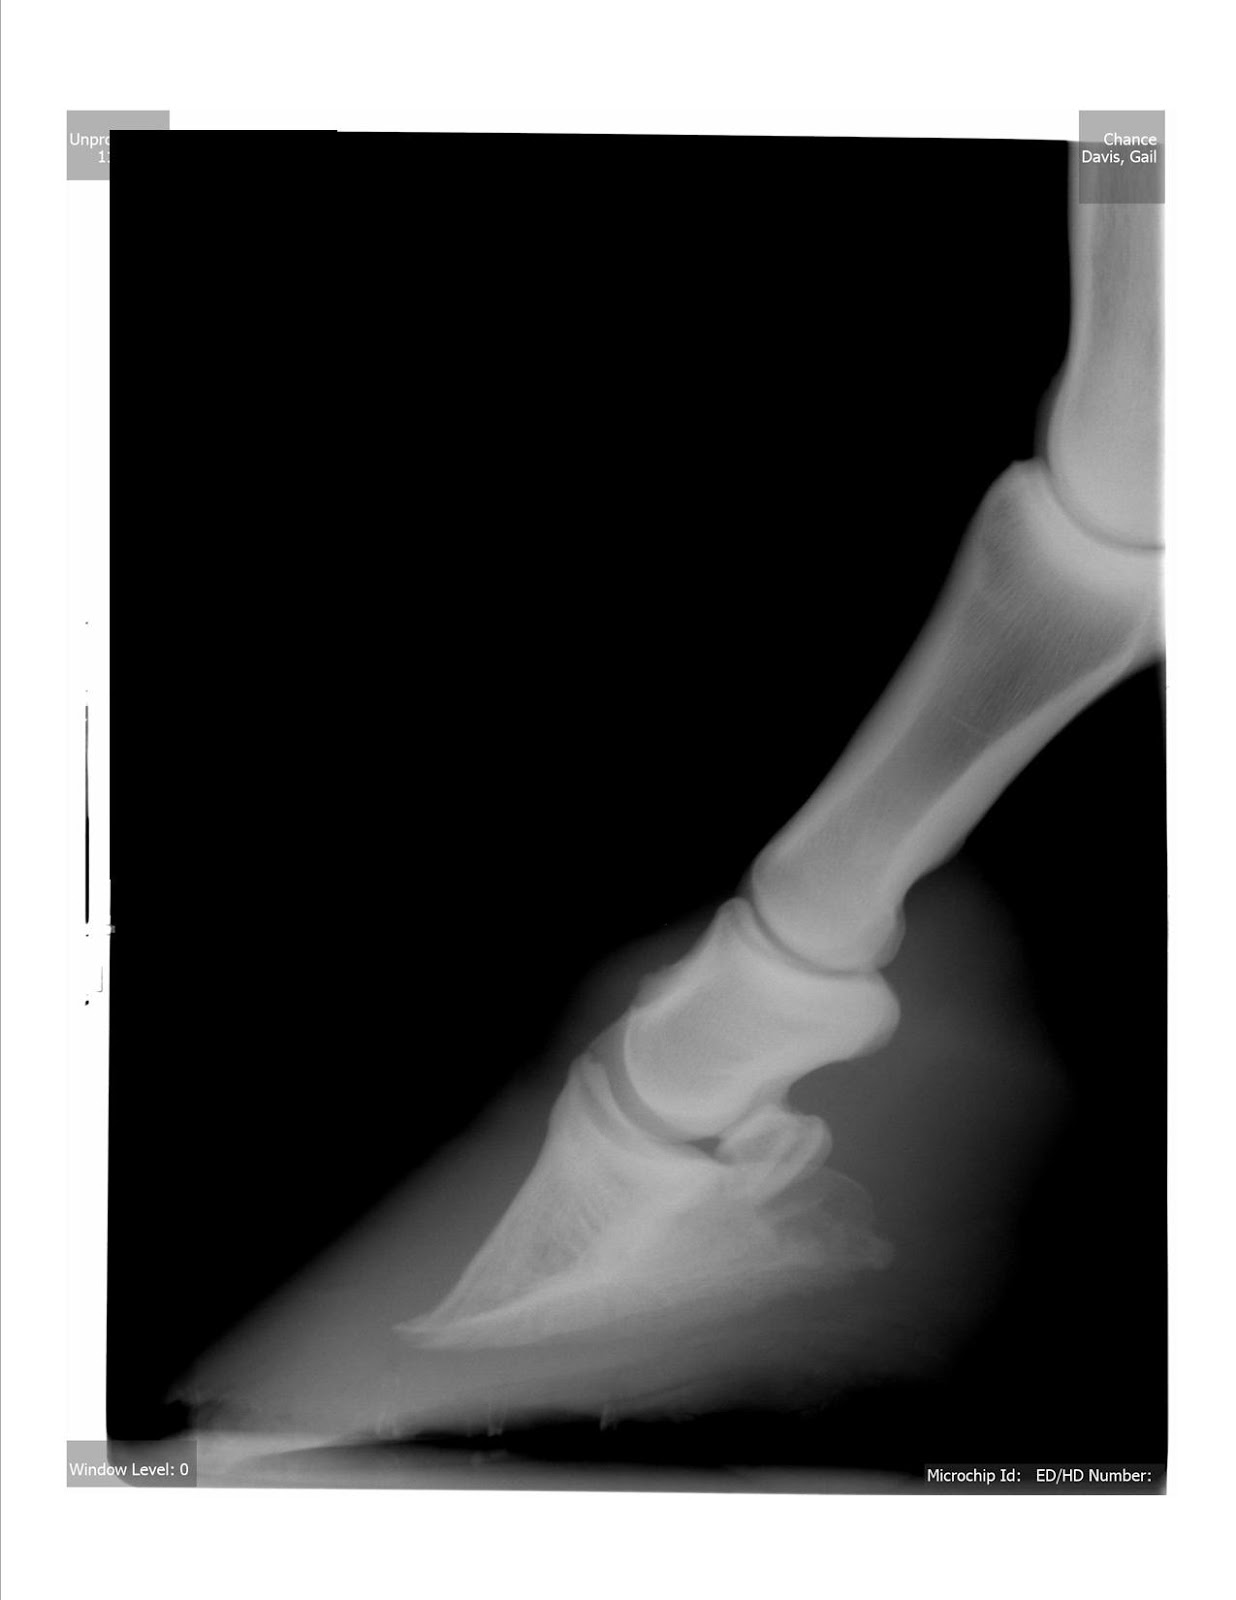

Chronic Laminitis 2 This is a classic case of a horse affe… Flickr Laminitis Horse Abscess Laminitis is the inflammation and subsequent separation of the laminae of the hoof. When the laminae separate, your. The hallmark clinical sign is severe lameness with bounding digital pulses. Vern dryden talks about why horses with laminitis might be more prone to hoof abscesses. In most cases hoof abscesses resolve completely without the time, expense, complications, and varied prognoses that. Laminitis Horse Abscess.